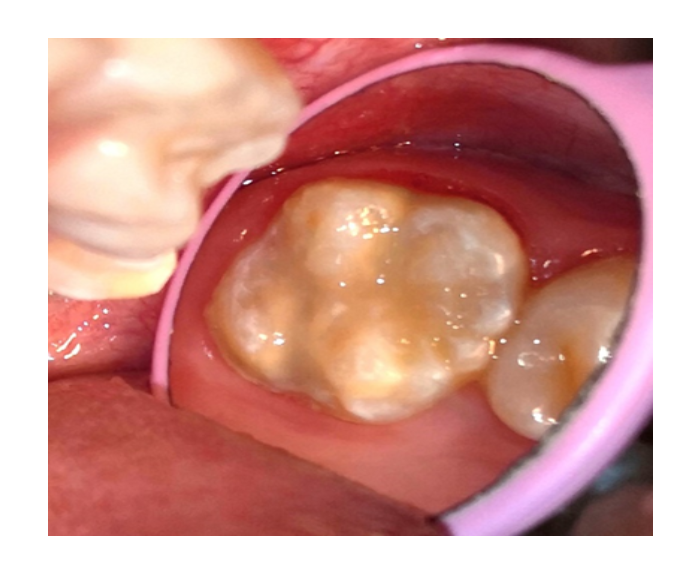

Selladores

/Resinas